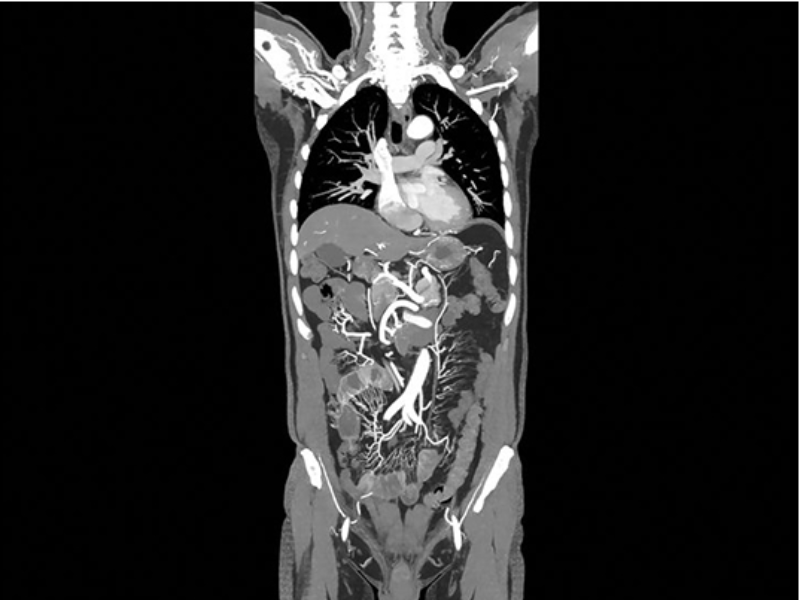

One-Beat Cardiac Scan Combined with Fast Helical CTA Scan